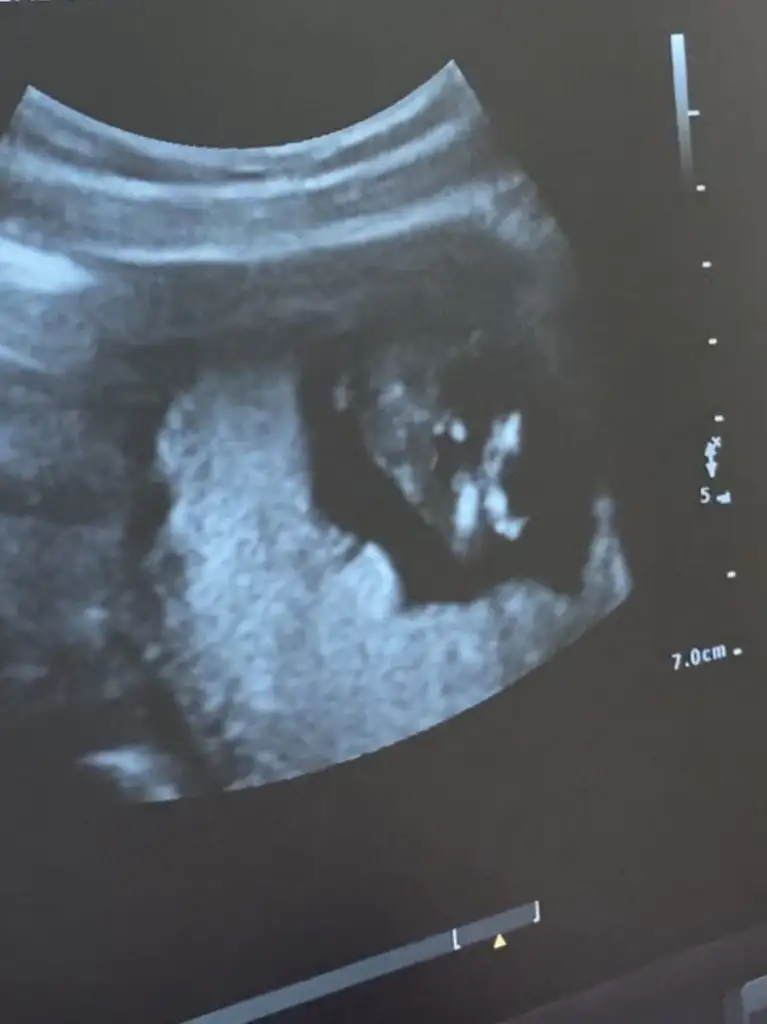

canım senin attıgın usg de bebegi yandan görüyoruz ya ben kız gibi hissettim inan icimden öyle geldi kendi usg görüntülerime baktım video dan hep bir cıkıntı var bana erkek dendi 12. hafta dan beri sana erkege benziyor derken bacaklarının arasını gösterdi mi dr şuan pc den yazıyorum telden girip 14. hafta daki usg bacaklarının arasını atıcam hala senin kızın olucak gibi geliyor bana hayırlısı ama öyle geliyor ne yapayım :)

05F0CAE0-68C6-4422-A622-09AF83EA4B50.webp